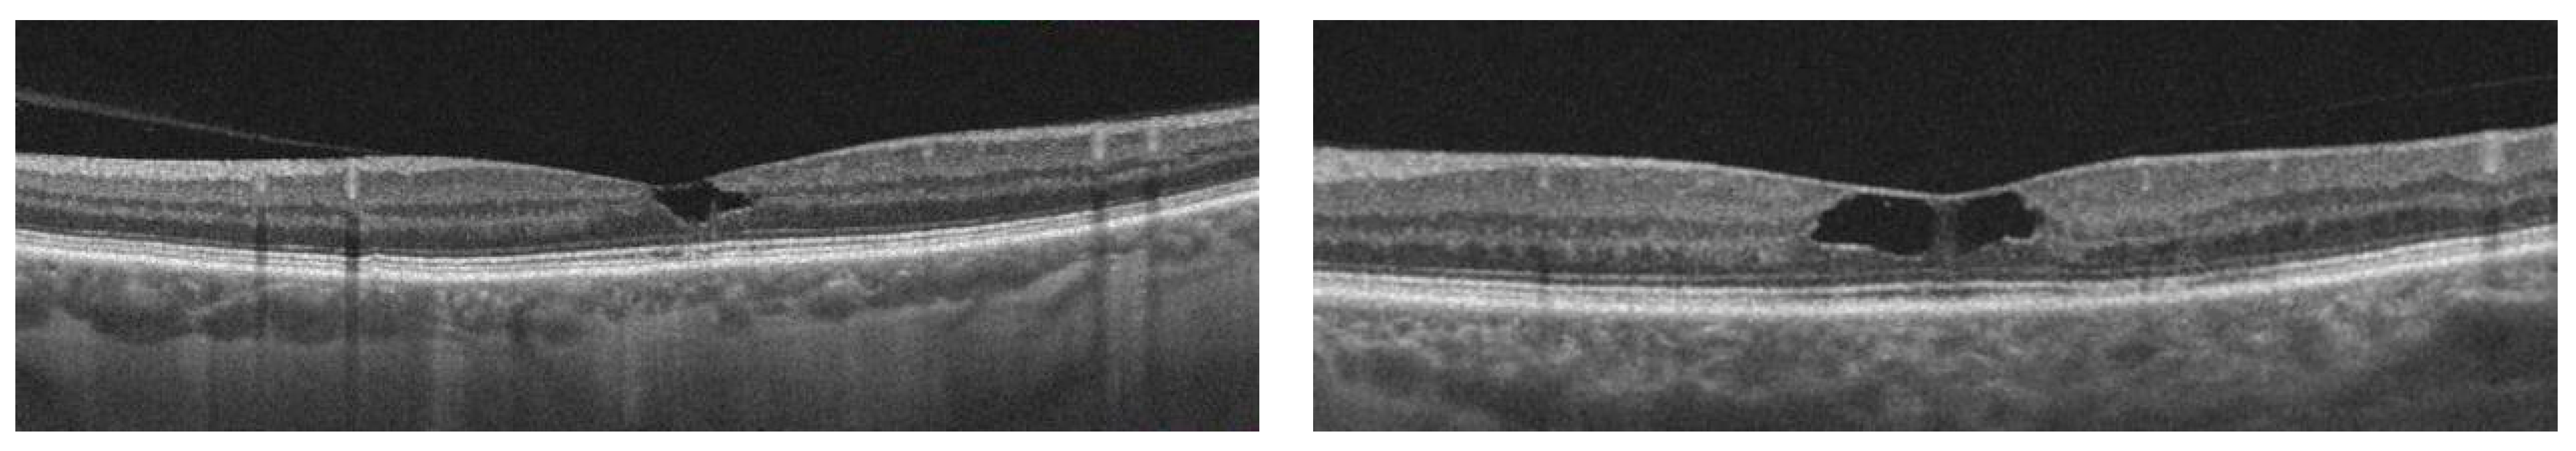

| Shi et al. [31] | 2019 | 100 eyes | DLS 14 | Qualitative biomarker | Identification of type 1 MNV in eyes with nonexudative AMD | DLS 14 has good predictive values for identifying type 1 MNV 2 | OCT 2 | Predictor |

- Shi, Y.; Motulsky, E.H.; Goldhardt, R.; Zohar, Y.; Thulliez, M.; Feuer, W.; Gregori, G.; Rosenfeld, P.J. Predictive Value of the OCT Double-Layer Sign for Identifying Subclinical Neovascularization in Age-Related Macular Degeneration. Ophthalmol. Retin. 2019, 3, 211–219. [Google Scholar] [CrossRef]

- Sheth, J.; Anantharaman, G.; Chandra, S.; Sivaprasad, S. “Double-layer sign” on spectral domain optical coherence tomography in pachychoroid spectrum disease. Indian J. Ophthalmol. 2018, 66, 1796–1801. [Google Scholar] [CrossRef]